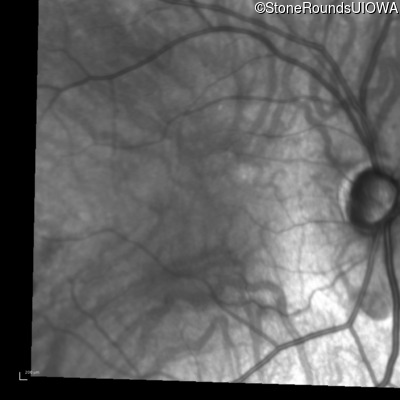

Age at visit: 26 years

This 26 year old man had significant myopia since childhood and uncorrectable reduction of acuity since his mid teens. Optic nerve abnormalities were noticed on a routine exam at age 5 and a diagnosis of Retinitis Pigmentosa was suggested. His medical history is also positive for profound hearing loss at birth and type 1 diabetes mellitus.

Age at visit: 29 years